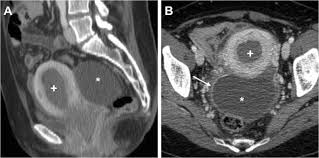

You see, women have two of these cul-de-sacs. One’s in the front of the uterus, between the uterus and the bladder. This is called the anterior cul-de-sac. The other cul-de-sac is behind the uterus, between the uterus and the rectum (your bottom). This one is called the posterior cul-de-sac.

These cul-de-sacs are important because they can hold fluid. During an ultrasound, your doctor might look for fluid in these cul-de-sacs. This could be a sign of several things, like:

Fluid accumulation in the cul-de-sac, also known as Douglas’s pouch, can occur due to various reasons. One common cause is ovarian cysts. These fluid-filled sacs on the ovaries can rupture or leak, leading to free fluid in the cul-de-sac.

Let’s explore the connection between ovarian cysts and fluid accumulation in the cul-de-sac in more detail. Imagine the ovaries as two small organs nestled within the pelvic cavity. They produce eggs and hormones essential for the female reproductive system. Sometimes, fluid-filled sacs, known as cysts, can develop on the ovaries. These cysts can vary in size and can either be benign (non-cancerous) or malignant (cancerous).

Now, let’s focus on the scenario of a ruptured or leaking ovarian cyst. When a cyst ruptures, the fluid inside spills out, creating a pool of free fluid in the pelvic cavity. This fluid finds its way to the cul-de-sac, the lowest point in the pelvic cavity, where it can accumulate. The amount of fluid accumulation can vary depending on the size of the ruptured cyst.

In most cases, the fluid in the cul-de-sac is benign and will be absorbed by the body naturally. However, if the fluid is significant or if the cyst is cancerous, it can cause symptoms like abdominal pain, bloating, or irregular bleeding. In these situations, medical intervention may be necessary to drain the fluid and address the underlying cause.